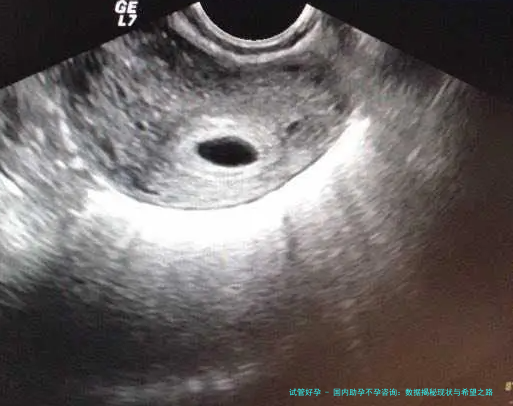

在技术层面,国内助孕手段可谓日新月异。试管婴儿技术从早期的成功率不足30%,提升到如今的50%以上,这得益于基因筛查和胚胎培养技术的突破。例如,近年来,PGD(胚胎植入前遗传学诊断)技术的广泛应用,帮助许多家庭避免了遗传疾病风险。数据表明,2020年至2023年,国内试管婴儿周期数年均增长15%,其中35岁以上女性的成功率提高了近10%。但话说回来,技术虽先进,却非万能。成本高、周期长的问题依然存在,许多普通家庭望而却步。我有个亲戚就曾尝试试管婴儿,花了近20万元,经历了多次失败才最终成功。这让我想到,技术发展需要更多普惠政策支持,不能只停留在高端市场。